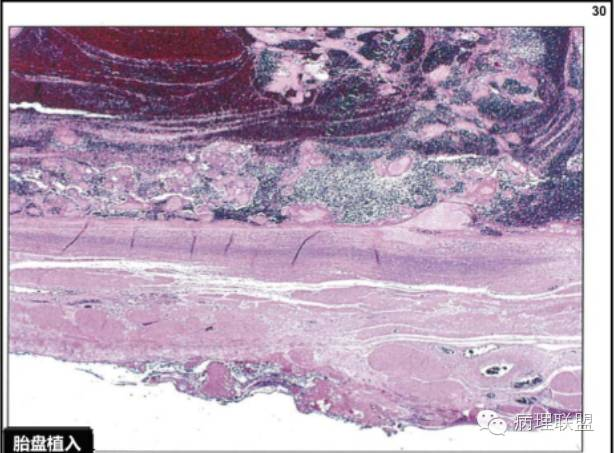

请教各位老师一个问题:一个36岁的女性,停经4个月,引产胎儿排出后胎盘未排出,然后临床刮取残留组织送检,临床考虑胎盘粘连,镜下见胎盘组织,部分区域坏死,未见到平滑肌,请问我应该怎么发报告?胎盘粘连是不是不能在刮宫标本中诊断?(晋城市人民医院病理 张勇提供,致谢!)